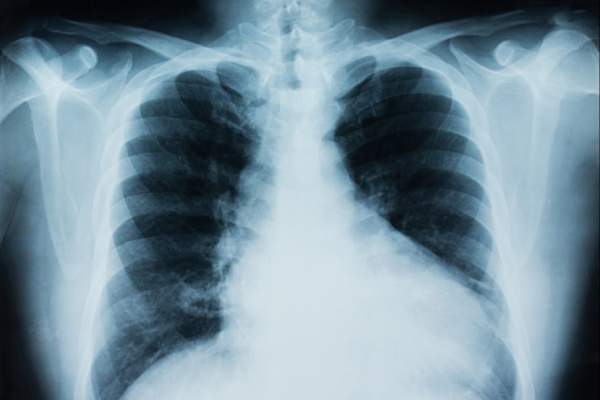

7 Ways Your Loved Ones Can Reduce Their Lung Cancer Risk

Because your immediate family members may be at increased risk of developing lung cancer if you too have the disease, here are some tips to stack the odds in their favor.